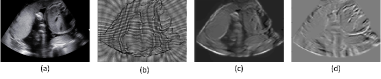

Refer to caption

Figure 1: Generated images based on JD and CV: (a) The original ultrasound image, (b) The grid image, (c) The image formed by JD, (d) The image formed by CV.